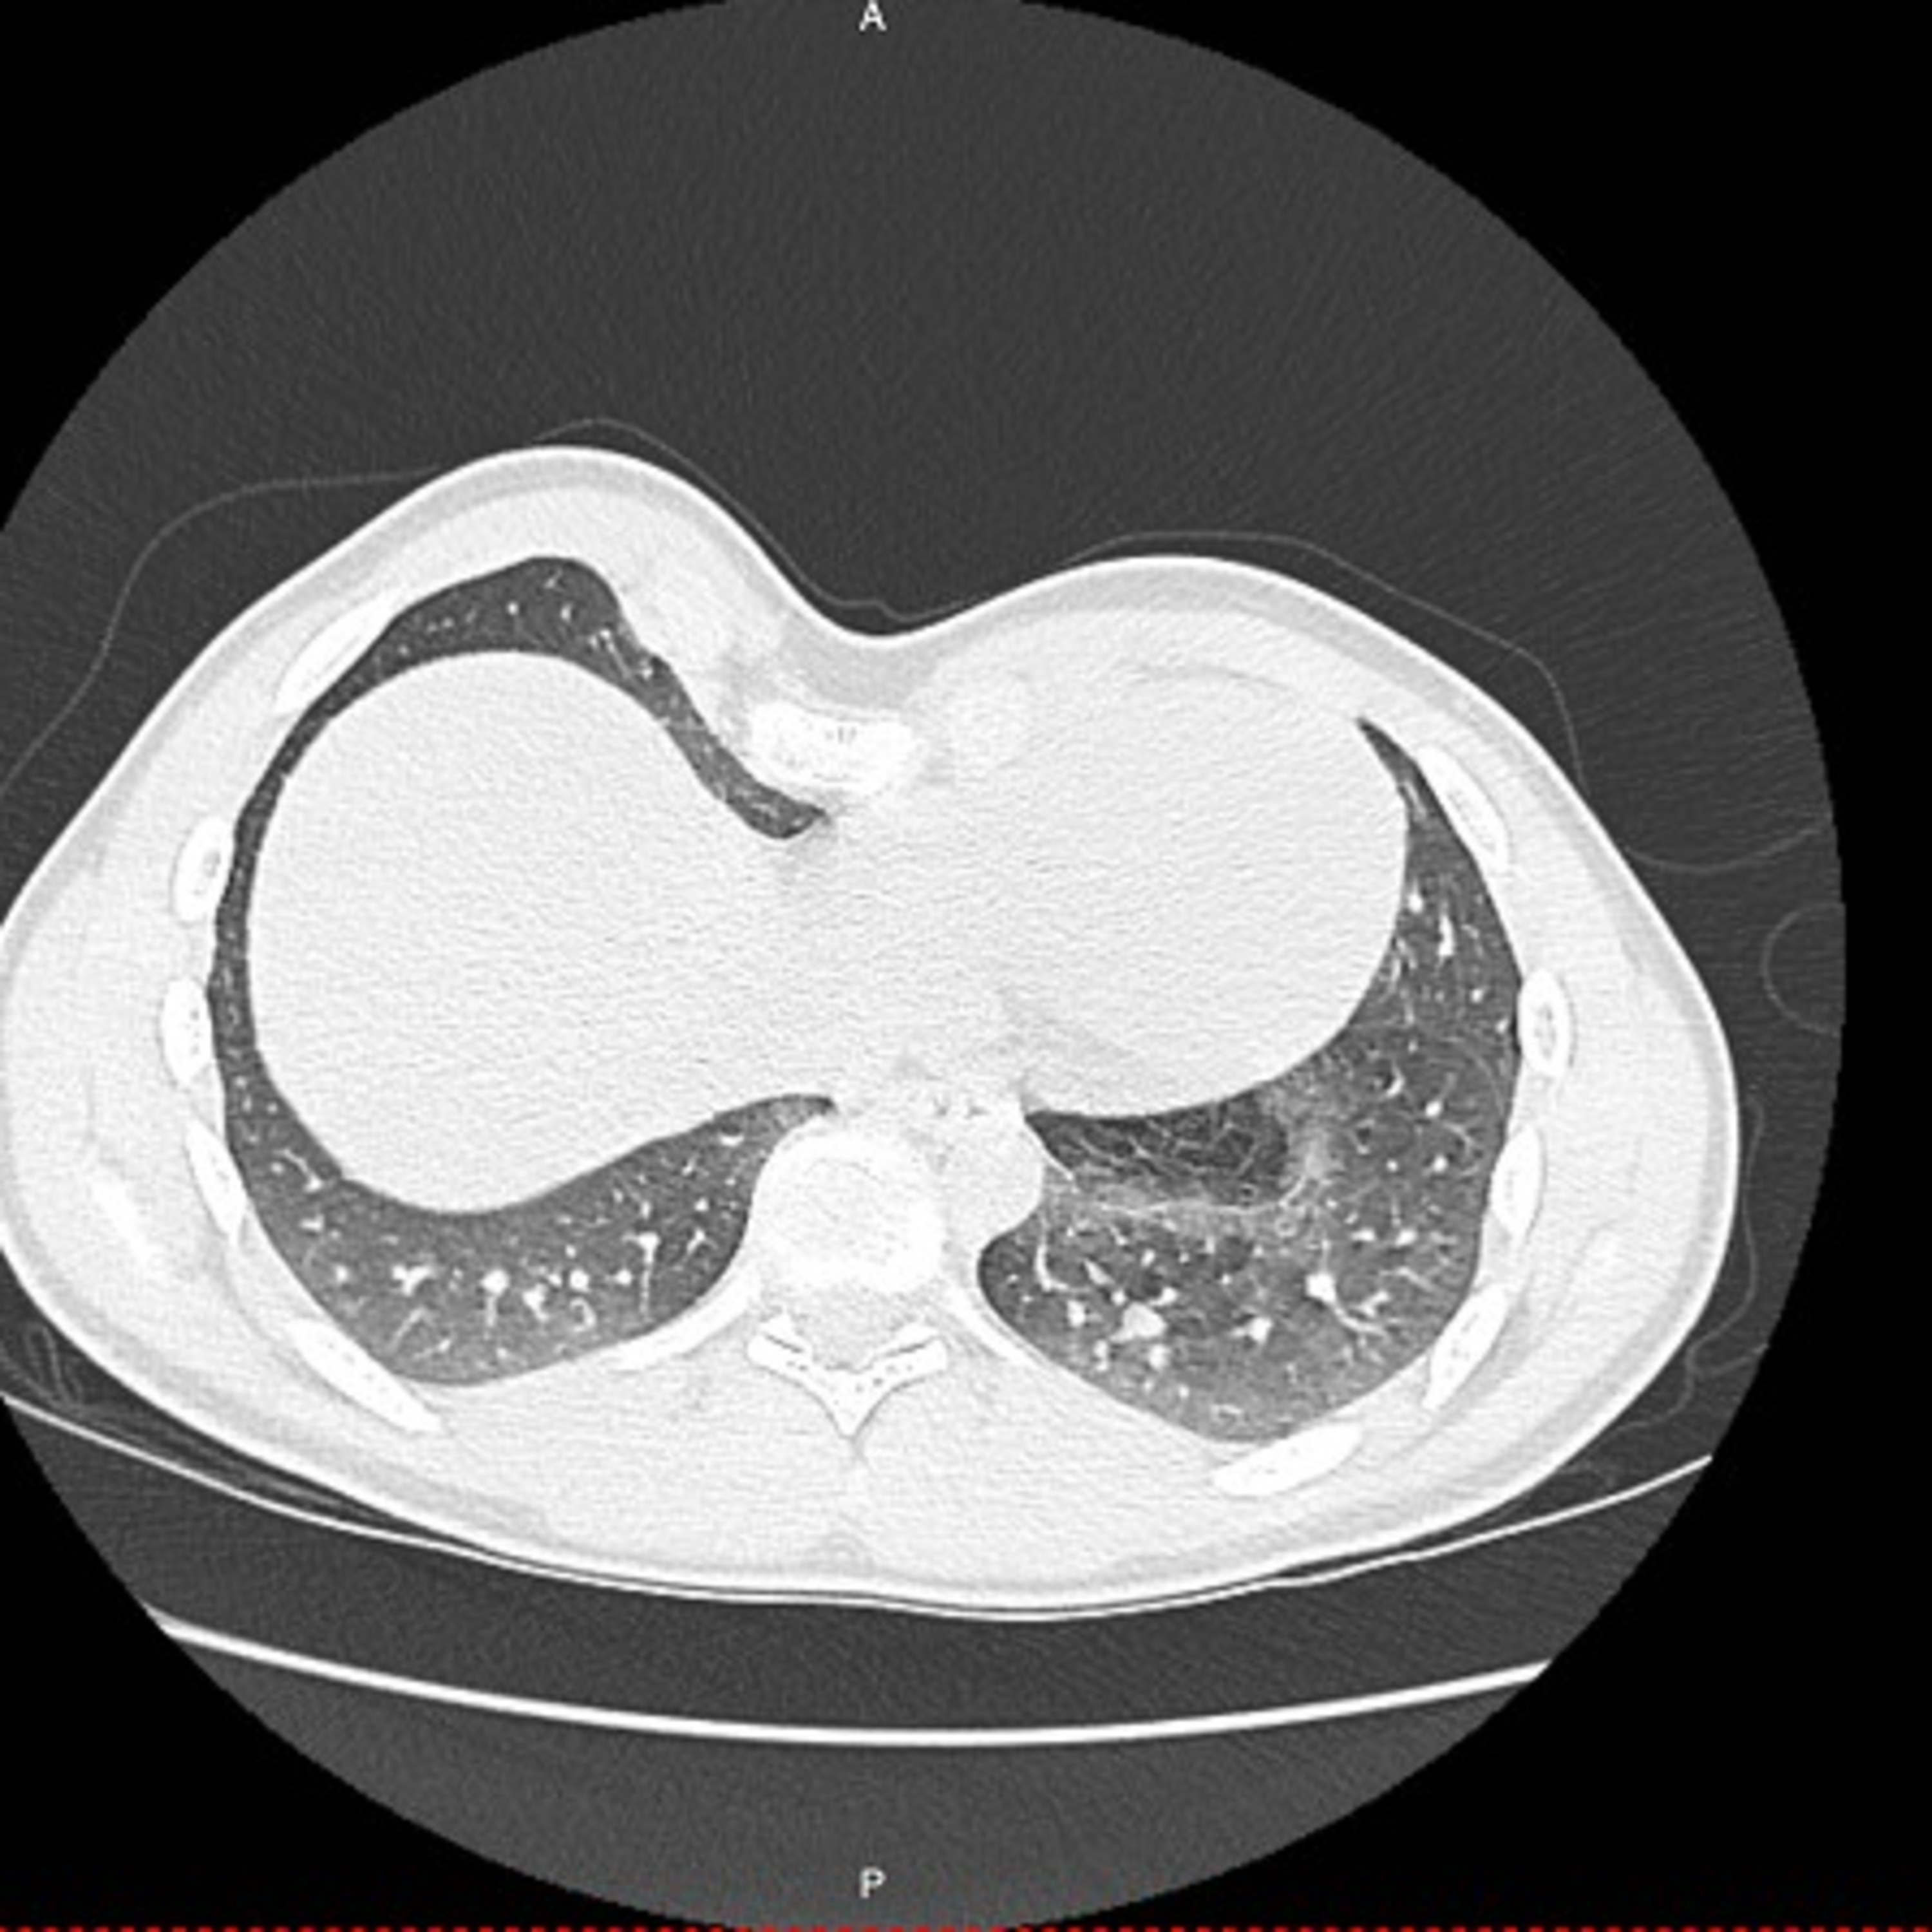

For a long time, deformities of the chest wall, such as pectus excavatum, a condition where the chest appears to have sunken, remained untreated or were treated using crude and invasive techniques. However, thanks to innovations led by surgeons such as Prof. Donald Nuss of Eastern Virginia Medical School, these procedures have undergone a remarkable transformation. Such work has shifted the paradigm from radical surgery to minimally invasive solutions, changing lives and restoring confidence for countless patients. Now, a Review Article published in the African Journal of Thoracic and Critical Care Medicine, and co-authored by Prof. Donald Nuss and Dr. Ivan Schewitz of the Department of Cardiothoracic Surgery at the University of Pretoria, South Africa, charts the remarkable progress in treating pectus excavatum.